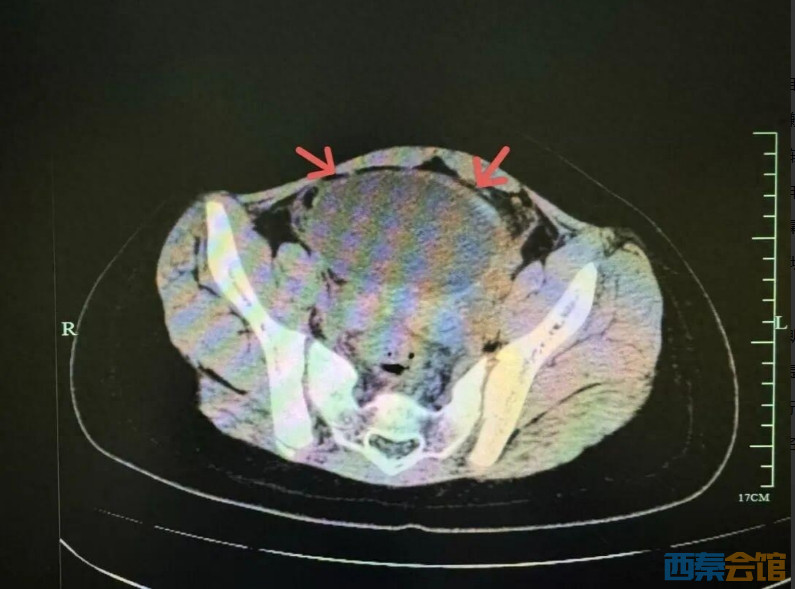

孩子肚子疼,还吐, 是不是吃坏东西了?” 最近气温骤降 10岁女孩小吉(化名) 突然闹起了肚子 又痛又吐 没想到背后隐藏着 意想不到的“**”! 浙江省中西医结合医院儿科医生检查后发现,小吉血象高、B超提示肠系膜淋巴结肿大,类似儿童常见的急性胃肠炎及肠系膜淋巴结炎,医生进行了抗感染和对症治疗。 治疗后,小吉呕吐的情况虽然出现了好转了,但肚子还疼,复查感染指标反而更高了,医生立即进行了更深入的排查。 据B超和CT显示 小吉的盆腔内有一个约9.5cm的巨大卵巢囊肿,并且已发生了 “蒂扭转”,这是一种需要紧急手术的妇科急腹症! 浙江省中西医结合医院儿科主任詹璐告诉记者,“这个囊肿以前可能就有,那段时间小吉的学校里要每天做仰卧起坐,造成这个囊肿一点点扭过去了。” 医生紧急对小吉进行了手术,手术十分顺利,保住了小吉的卵巢,避免了不可逆的伤害。詹璐表示“如果囊肿扭转时间长的话,一侧卵巢坏死就影响将来生育的功能。” 腔镜下照片 孩子肚子疼 这三种情况最会“伪装”  儿童急腹症在诊断上十分复杂 就像在迷宫里破案 孩子出现腹痛的症状 除了常见的肠胃炎 以下几种“善于伪装”的危急重症 必须一一排查 ↓↓↓  急性阑尾炎 典型特征是从上腹/脐周痛转移到右下腹固定疼痛。但儿童,尤其是幼儿,表达不清,可能只说全腹痛,查体时表现为哭闹、拒按右下腹。一旦拖延,可能导致阑尾穿孔,引发弥漫性腹膜炎,危及生命。 肠套叠 儿科特点:常见于2岁以内婴幼儿。典型表现为 “阵发性哭闹” ,间歇期可恢复平静,随后再次发作。同时可能出现 “果酱样”血便。如不及时复位,会导致肠坏死、穿孔。 卵巢囊肿蒂扭转 专发于女童。表现为突发下腹部剧痛,多为单侧,常伴恶心呕吐。因其症状与肠胃炎极其相似,最容易被忽略和误诊。扭转会卡断卵巢血液供应,短时间内即可导致卵巢缺血坏死,不得不切除,对孩子未来的生育能力和内分泌发育造成毁灭性打击。 孩子喊肚子疼时,家长不要轻易将腹痛归咎于“着凉”或“吃坏”。要观察疼痛的位置、性质、频率以及是否有呕吐、发热、大便异常。当医生建议进行B超等影像学检查时,请不要犹豫,这是洞察腹腔内情况最直观的“眼睛”。 特别提醒! 家有女童多留心 如果女孩出现持续或剧烈的下腹痛 一定要及时就医 排查妇科疾病 (来源:新闻坊)